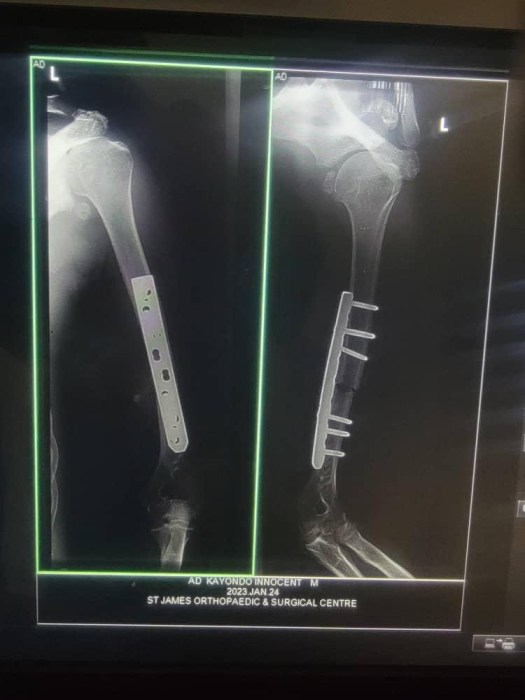

Dear friends sorry for the delay in writing an update, it’s been a difficult couple of months. I won’t give you the gory details but just tell you that Innocent and I have both survived! Innocent’s experience 4000 miles away in Uganda was very different to mine in a modern hospital in the UK but I think he probably moaned less than me, they’re made of tougher stuff out there!!

Soon after the operation Innocent went back to his village to recuperate with his mum helping to care for him just as she did in hospital where the nurses don’t play a caring role as they do here. You only get fed, washed, etc if a member of your family are there to look after you! Often you see whole families camped outside hospitals while their loved ones are having treatment inside.

Innocent will return to the hospital for a check up and possibly some physio sometime soon. Knowing him he’ll be very frustrated not being able to carry out work round his farm and be the usual hands-on dad and carer for his family. He’s being seriously nagged by me regularly to be patient and let his body heal after the trauma it’s suffered over the last few months. Obviously I would love him never to get anymore seizures but being realistic I know I can only hope sincerely that he gets no more before his arm is strong enough to take the falls! Any prayers and thoughts for him will be appreciated.

I will always be so grateful to Bosco who found a qualified surgeon to operate on Innocent after the terrible experience he had using ‘local’ method of repairing broken bones! He was very very scared about the anaesthetic though, believing he wouldn’t wake up again. The local ways used no anaesthesia and just involve daily massage and bandages made taught by turning sticks!

It was good that I ended up having my operation a day before Innocent as it encouraged him to go ahead too, though Bosco said it was rather touch and go right up until the last minute especially as he had been listening to people in his village had been discouraging him by talking about the benefits of traditional medicine and witchcraft! But I really felt Innocent and I were there for each other!

Latest news from Innocent who as you know helps me with my projects (we previously sponsored him through uni but no one will employ him because of his epilepsy!) He’s just had another X-ray and it showed his bones mended. Relief all round! The doc says because his arm is very strong he can start lifting 5kg and then after another two months 100kg! Innocent has asked me to thank those of you who helped my hubby and I pay for his operation. Well worth the £800 it cost to prevent him losing his arm and being crippled for life, an enormous disadvantage when you are a farmer!